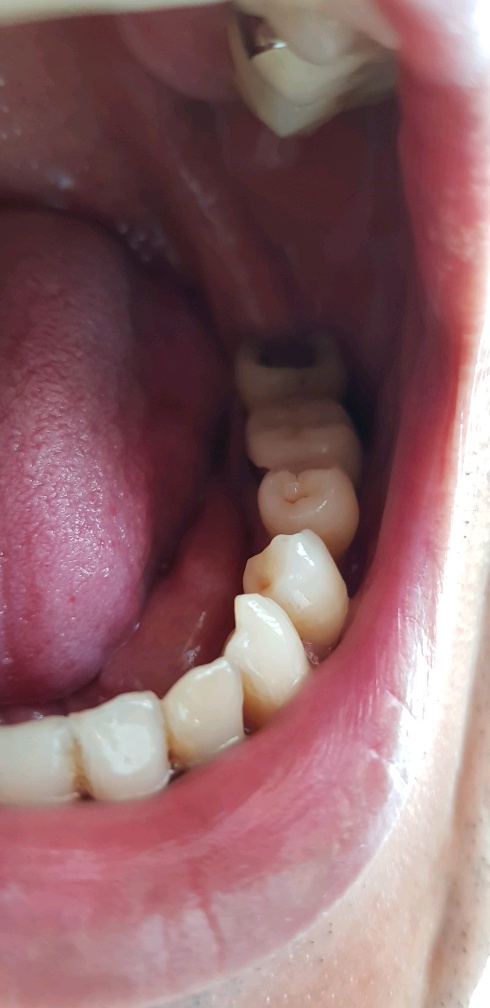

왠쪽 어금니 뽑기전 마지막 사진...

이렇게 뺄거였으면 차라리 2주전 교정치과에서 거금들여서 치료 안하는 거였는데 ㅡㅡ;;